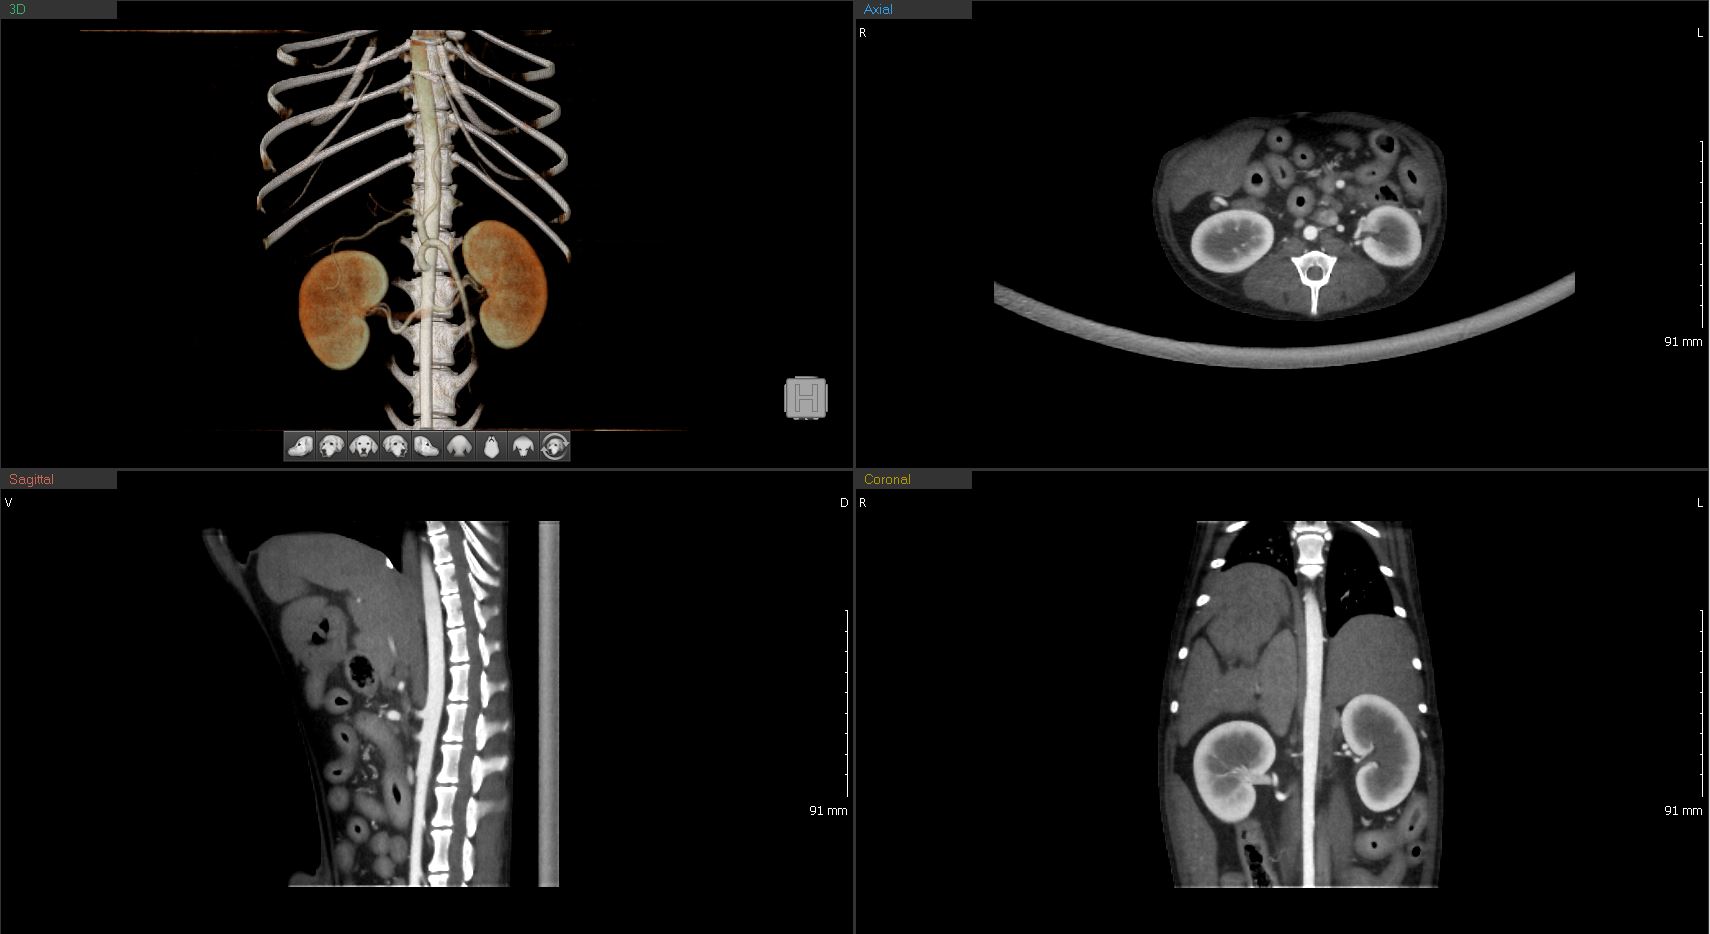

복부간, 비장, 소화기계, 비뇨기계 등의 복강의 장기

복부 CT

복부